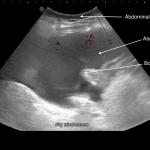

ABDOMINAL COLOR DOPPLER ULTRASOUND

Key features of ascites seen in this imaging modality are:

- Anechoic nature: ascites will allow sound waves to pass through it, so it will appear black/dark on ultrasound.

- Absence of color doppler signal: there should be no flow signal seen throughout the ascites. Ascites should not move around if the patient is still, and it should not contain vessels.

The gallery below organizes examples of how ascites will appear on abdominal color doppler ultrasound. Click on the thumbnails below to open up the gallery: